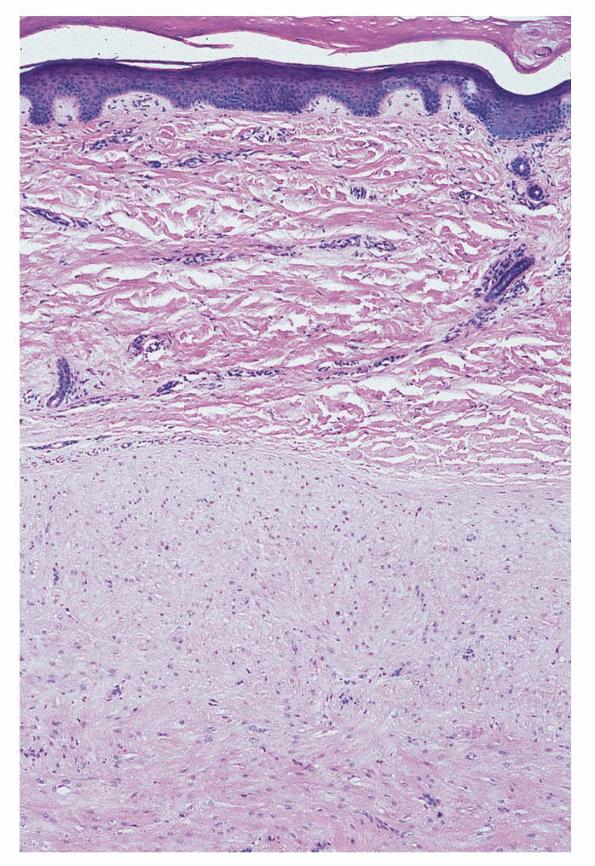

Angioleiomyoma =العضلوم الوعائي